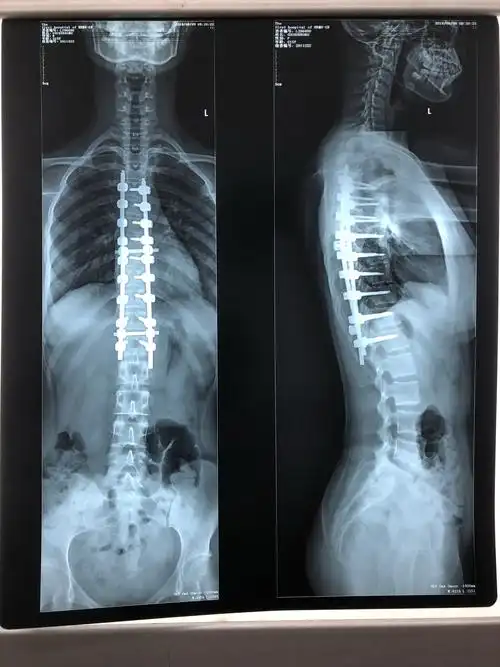

特发性脊柱侧弯的治疗!附手术前后对比照片! - 好大夫在线